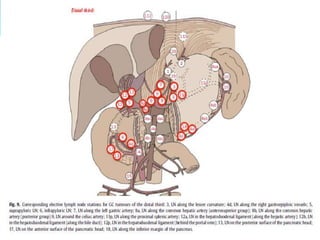

Extent of lymphadenectomy

Japanese Research Society for the study of Gastric Cancer

 N1 : LN stations 1-6 (perigastric LN)

 N2 : LN stations 7-11 (extra perigastric LN)

 N3 : LN stations 12-14 (hepatoduodenal LN)

 N4 : LN stations 15-16 (paraaortic LN)

 Removal and analysis of at least 15 LNs is required.

Lymph Node Dissection

D1- removal of involved proximal and distal stomach with

margin or total gastrectomy along with removal of lesser and

greater omental lymph nodes

(Includes right and left cardiac lymph nodes, right gastric

artery and supra and infra pyloric nodes)

D2 – D1 plus removal of all nodes along left gastric artery,

common hepatic artery, celiac artery, splenic hilum and artery

D3 – D2 plus omentectomy, clearance of porta hepatis lymph

nodes and para-aortic lymph nodes, splenectomy,

pancreatectomy.